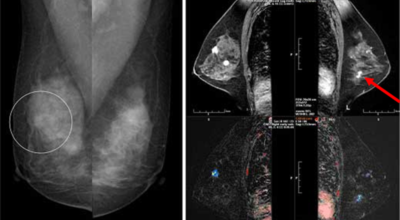

개인마다 유방암 초기증상은 다르게 나타날 수 있어요. 유방암은 우리나라 여성암 1위인만큼 많은 여성분들이 유방암 초기증상에 대해 관심이 많아 검사를 많이 하는 추세입니다. 스트레스를 많이 받는 젊은 여성들도 유방 통증으로 진단을 받는 경우가 늘고 있다고 하죠. 경우에 따라서는 유방암 초기증상이 없을 수도 있답니다. 유방암 자가검진 후 증상이 발견된다면 빨리 병원에 방문하는 것이 좋아요.

보통 응어리가 잡히는 분들의 40%는 물혹으로 가벼운 질병으로 바로 치유가 되는 경우가 많은데요 20~30%의 확률로 유방암 초기증상일 가능성이 있다고 하네요. 따라서 매일같이 자신의 가슴을 마사지 해주시다 어느날 응어리가 잡히게 된다면 유방암 검사 초기에 받아 보시기를 권해 드리겠습니다.